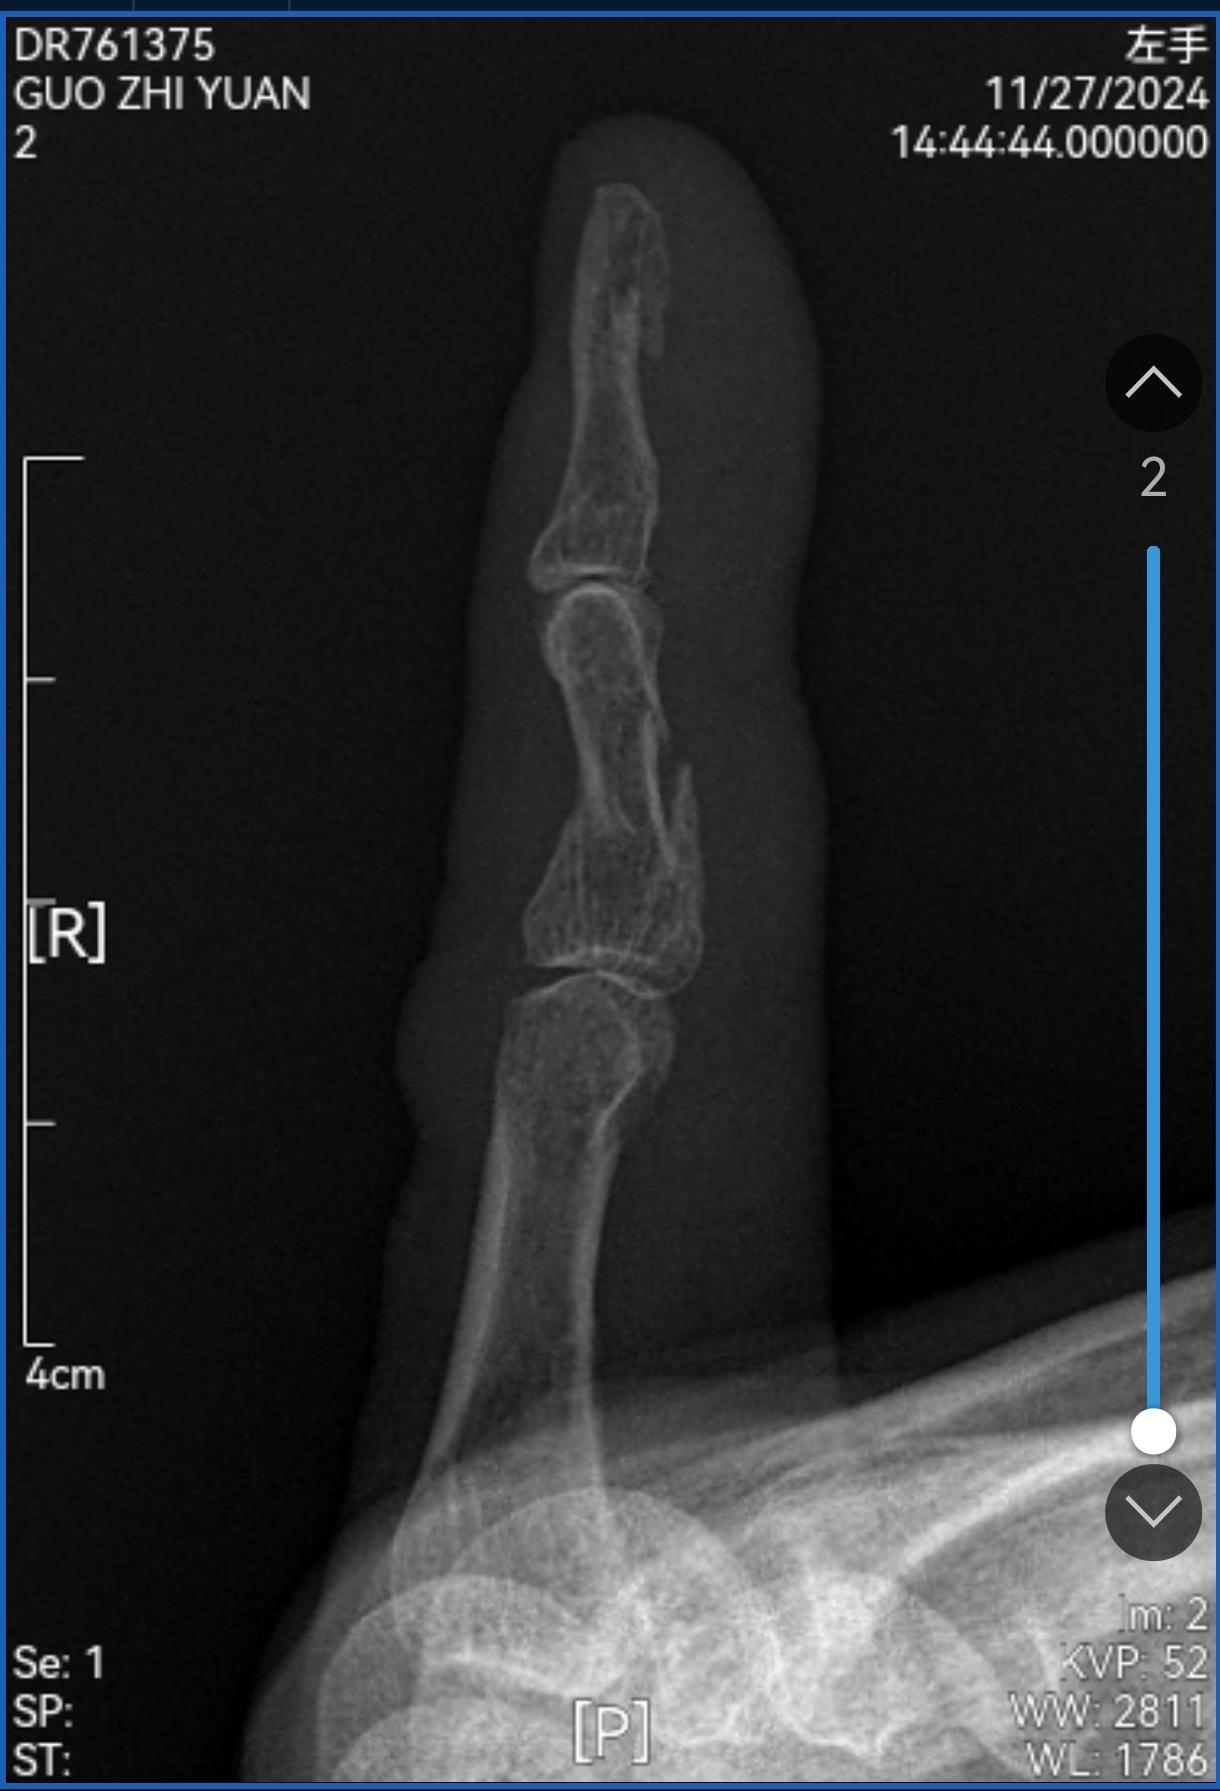

2024-11-28 14:02

中医正骨